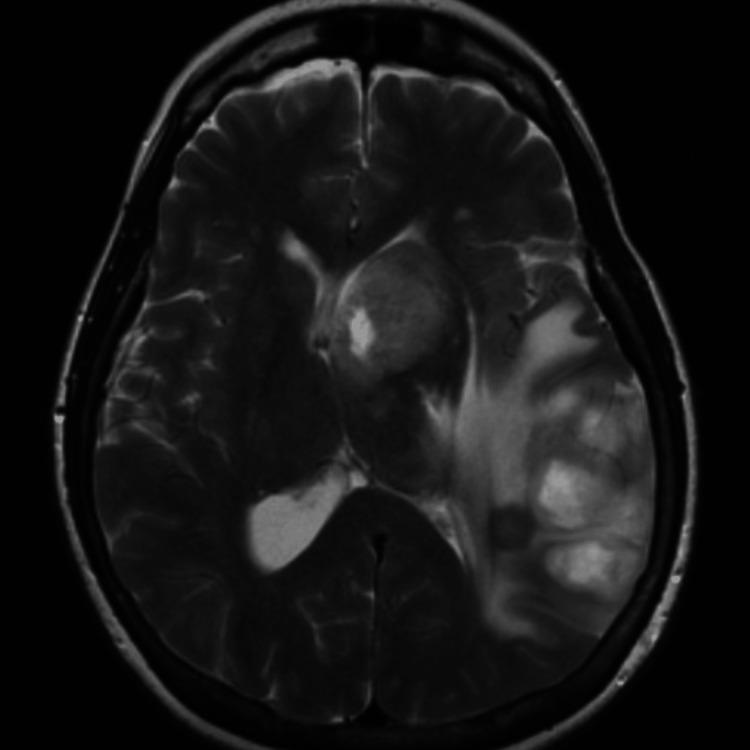

Coronavirus disease 2019 (COVID-19) is caused by the severe acute respiratory distress syndrome coronavirus 2 (SARS-CoV-2), which became a pandemic in March 2020. Since that time, research has shed light on this disease's pulmonary, cardiac, and hematologic complications. However, we are still unraveling the complex neurologic sequelae of COVID-19. Here we present the case of a 58-year-old female who presented with weakness, gaze preference, and aphasia. She was diagnosed with a stroke which was managed medically. The patient returned two weeks later with memory loss and aphasia. An MRI was consistent with temporal lobe encephalitis, although a lumbar puncture was unremarkable. A polymerase chain reaction (PCR) test for COVID-19 was positive. Treatment was initiated for viral encephalitis with patient improvement. She was discharged a second time, and approximately three months later, she presented again with unrelenting headaches. Further imaging revealed a mass that was determined to be a grade IV glioma. Cases of glioma after viral encephalitis have been studied, but a clear link with COVID-19 has not been established.

2019冠状病毒病(COVID-19)由严重急性呼吸综合征冠状病毒2(SARS-CoV-2)引起,该病毒于2020年3月成为大流行病。自那时以来,研究已揭示了这种疾病的肺部、心脏和血液学并发症。然而,我们仍在逐步了解COVID-19复杂的神经后遗症。在此,我们报告一例58岁女性病例,该患者表现为虚弱、凝视偏好和失语。她被诊断为中风并接受了药物治疗。两周后,该患者因记忆力减退和失语再次前来就诊。磁共振成像(MRI)结果与颞叶脑炎相符,尽管腰椎穿刺检查无异常发现。COVID-19聚合酶链反应(PCR)检测呈阳性。针对病毒性脑炎开始进行治疗,患者病情有所改善。她第二次出院,大约三个月后,她再次因持续性头痛前来就诊。进一步的影像学检查发现一个肿块,经诊断为IV级胶质瘤。病毒性脑炎后发生胶质瘤的病例已有研究,但尚未确定与COVID-19有明确关联。